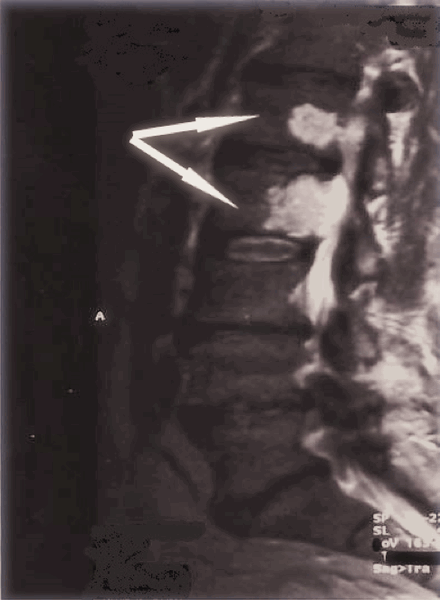

Опухоль позвоночника на МРТ (обозначена стрелками)